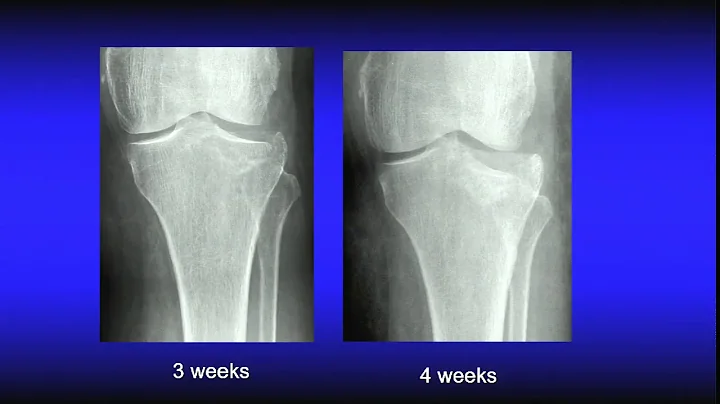

Challenges with tibial plateau fractures - Pa...

with Dr. J. Spence Reid, Dr. Kenneth Egol, Dr. William DeLong, Dr. Chr...

• Duration:

44m 47s